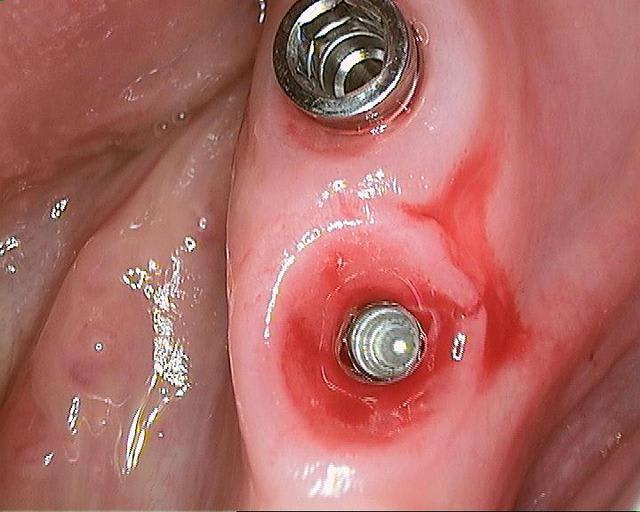

des photos d'un cas d'aujourd'hui avec le shuttle retiré ( 8 premières photos)

les 4 dernières c'est avec le foret , la dernière photo c'est un cas d'extraction implantation d'aujourd'hui aussi on voit la nouvelle alvéole après le forage ( désolé pour la qualité de photo...)